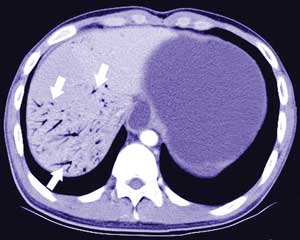

A 17-year-old man with a slim build presented with recurrent postprandial epigastric fullness and bilious vomiting. He was acutely unwell. An abdominal radiograph showed gastric and duodenal distension. Contrast computed tomography scans showed proximal duodenal dilatation (Box, A, arrow), with a triangular-shaped duodenum, extensive hepatic portal venous gas (Box, B, arrows), and a massively distended stomach.

Superior mesenteric artery syndrome with hepatic portal venous gas was diagnosed. This syndrome occurs when the fat pad between the superior mesenteric artery and its origin at the aorta is lost, causing a sharp, narrow angle at the aortomesentery junction. The third portion of the duodenum is compressed and becomes obstructed when passing through this angle.1 Hepatic portal venous gas can develop as a result of bowel ischaemia.